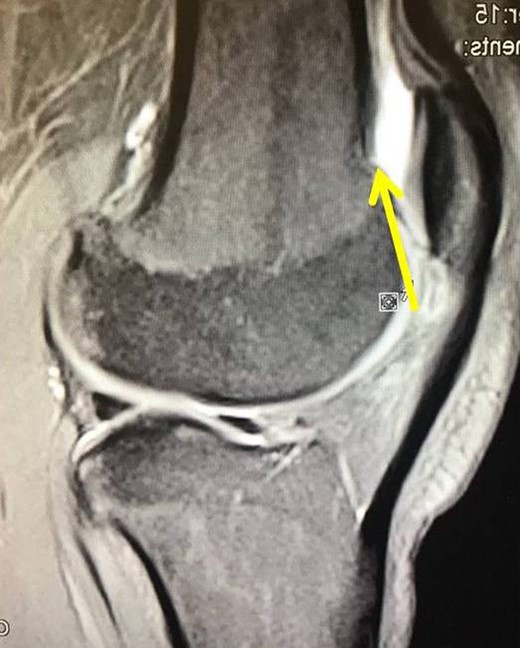

X-rays revealed an extra-articular mass at the medial aspect of the distal femur (Fig. 1A). Magnetic resonance imaging (MRI) confirmed the radiograph findings and no meniscal and ligament rupture or chondral defects were revealed. These characteristics were consistent with osteochondroma (Fig. 1B). Under general anesthesia, a standard antero-lateral portal used to access arthroscopically the knee. Cartilage surface, cruciate ligaments and menisci were normal. The osteochondroma was located extra-articularly, at the medial supracondylar side of the distal femur. Through a supero-medial portal and by perforating the capsule and a part of a medialis vastus muscle, the extra-articular lesion was reached arthroscopically (Fig. 2A). With an osteotome, the lesion was resected and removed with a grasper through the supero-medial portal (Fig. 2B). The remaining bony surface was abraded by a motorized shaver (Fig. 2C). The exostosis had maximum dimensions 3.1 × 2.5 cm. Histopathological examination confirmed the osteochondroma diagnosis.

(A) The X-ray depicting the exostosis (yellow arrow), (B) MRI depiction of the exostosis.